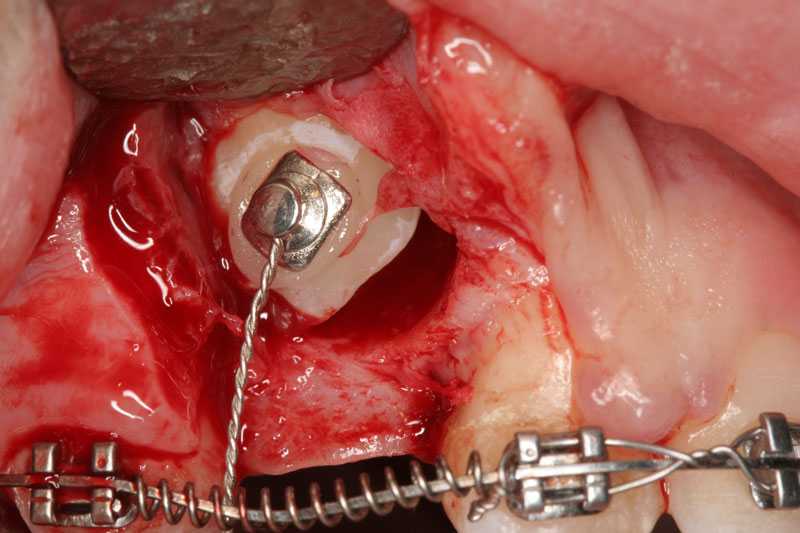

3β. αποκάλυψη εγκλείστων για ορθοδοντικούς λόγους.

- Χειρουργική αποκάλυψη εγκλείστων δοντιών για ορθοδοντικούς σκοπούς.

- Βασικές χειρουργικές τεχνικές και αρχές στη τοποθέτηση των εμφυτευμάτων και ανάπλαση ελλειμματικής φατνιακής ακρολοφίας μικρού η μέσου βαθμού.